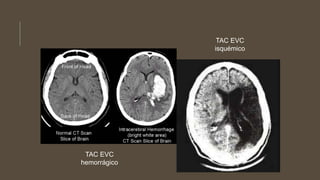

Imagenología:

TAC cerebro: para fase aguda

 Permite definir la naturaleza isquémica o

hemorrágica del EVC.

 Isquemia: Hipodensidades a partir de las 12-24h

del evento.

 Hemorragia: Aparecen inmediatamente como

hiperdensidades, revelan topografía, vol de la

lesión, repercusión a estructuras vecinas.

TAC EVC

hemorrágico

isquémico